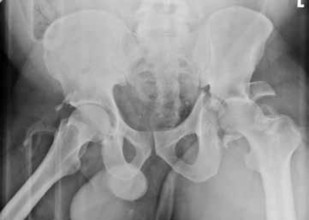

Q. 1Figure 1 is the radiograph of a 62-year-old woman who fell and sustained a left hip fracture. A radiographis shown in Figure 1. Which of the following preoperative risk factors is associated with the highest postoperative mortality rate?